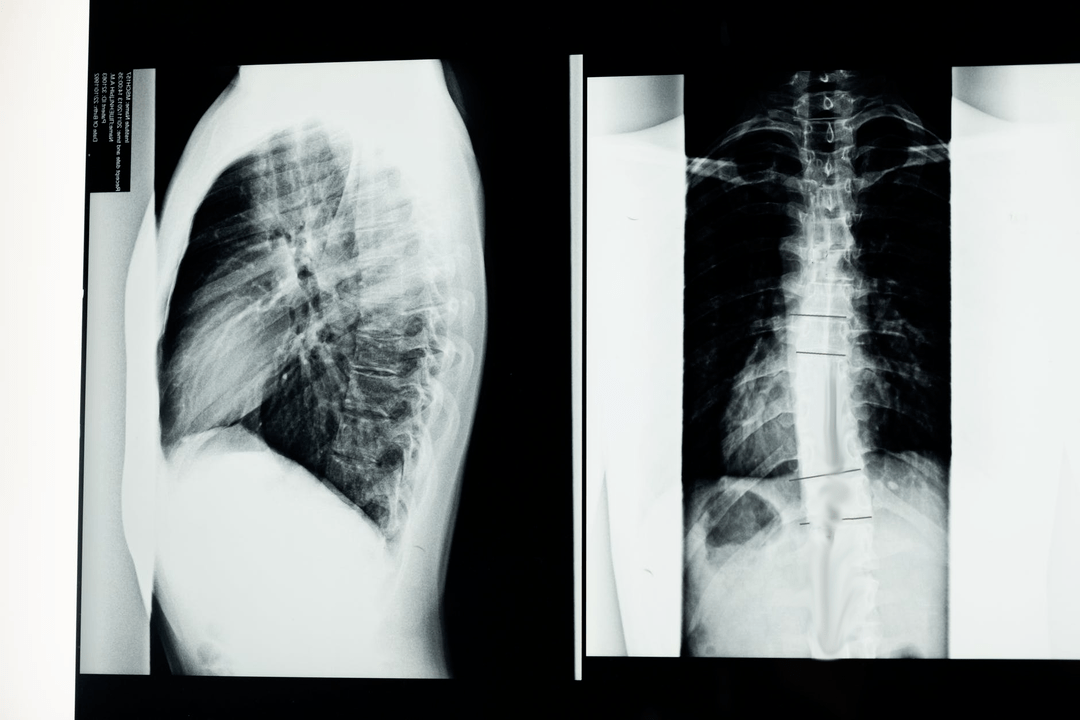

Antes de iniciar os estudos diagnósticos, o neurologista coleta o histórico médico do paciente e estuda cuidadosamente suas queixas. A osteocondrose tem sintomas comuns a algumas outras doenças, por isso é importante saber diferenciar as patologias. Os estudos de raios X ajudarão a confirmar o diagnóstico de osteocondrose: radiografia, mielografia e tomografia computadorizada.

Uma radiografia de levantamento permite obter uma imagem radiográfica da coluna vertebral ou de uma seção dela. Dessa forma, o médico poderá determinar o local afetado pela doença. Para maior clareza, explicaremos como a osteocondrose pode ser determinada pela radiografia: a imagem mostrará um estreitamento do disco intervertebral, a presença de crescimentos ósseos (osteófitos) ou uma alteração na forma do segmento espinhal.